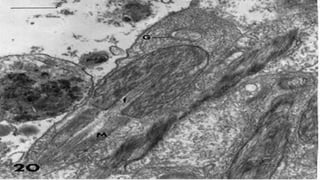

 Mitochondria migrate through actin filaments called

manchette to form the middle piece

Acrosome phase